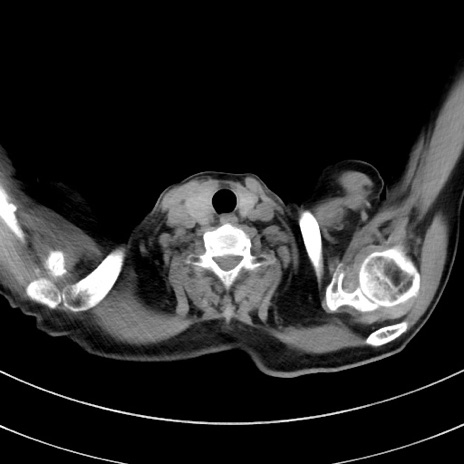

冠状断像